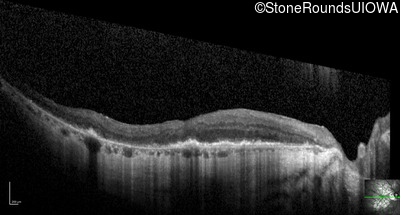

Optical Coherence Tomography - Left - 20/80 -1

Exemplar / OCT Stack